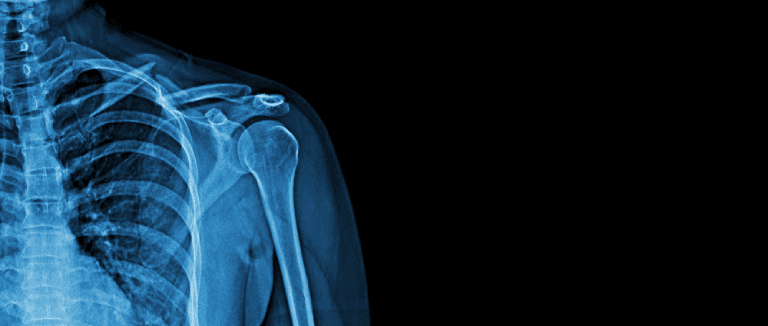

Total Shoulder Arthroplasty (TSA)

TSA is used to treat serious rotator cuff injuries or severe shoulder arthritis. This treatment replaces the left or right shoulder’s injured ball-and-socket joint with artificial parts.